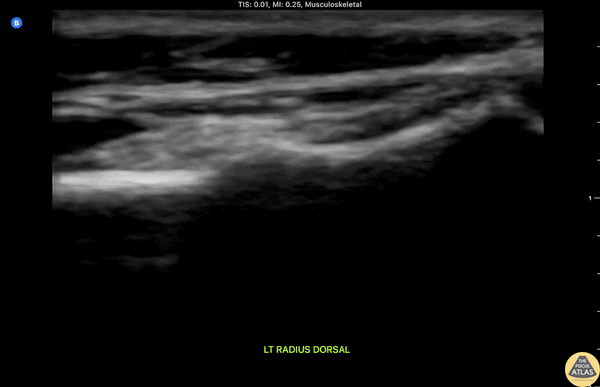

Clip shows longitudinal dorsal view of the radius with a "bump" in area of tenderness consistent with a torus or "buckle" fracture in a pediatric patient evaluated following a fall. Miguel Agrait MD CAQ-SM, Eddie Rodriguez MD FPD-AEMUS